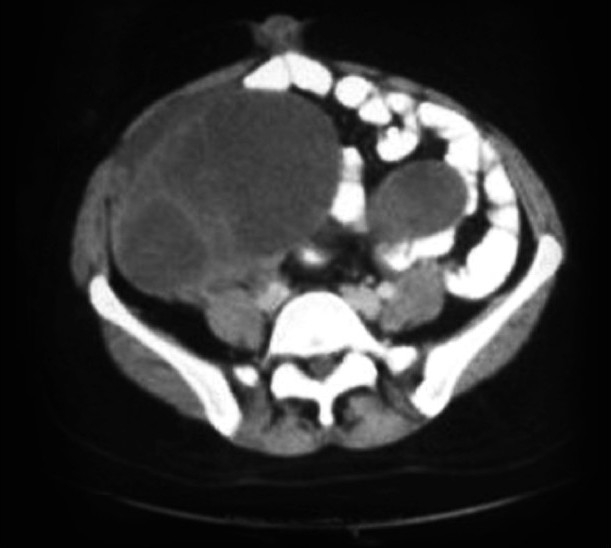

The CT scan of the abdomen [Figure 2] showed very large, bilateral, solid-cystic, heterogeneously enhancing abdominopelvic lesions extending from the bilateral adnexal regions to the abdomen. These lesions were abutting-involving the fundus and posterior wall of the uterus and also abutting the superior part of the urinary bladder with focal loss of intervening fat planes.

| Figure 2 CT scan of the abdomen showing adnexal mass and skin metastasis

Multiple small-to-medium sized hypodense heterogeneously enhancing lesions were seen in both lobes of the liver. Anterior abdominal wall deposits were present. There was a presence of retroperitoneal, diaphragmatic, and bilateral inguinal lymphadenopathy along with the ascites.